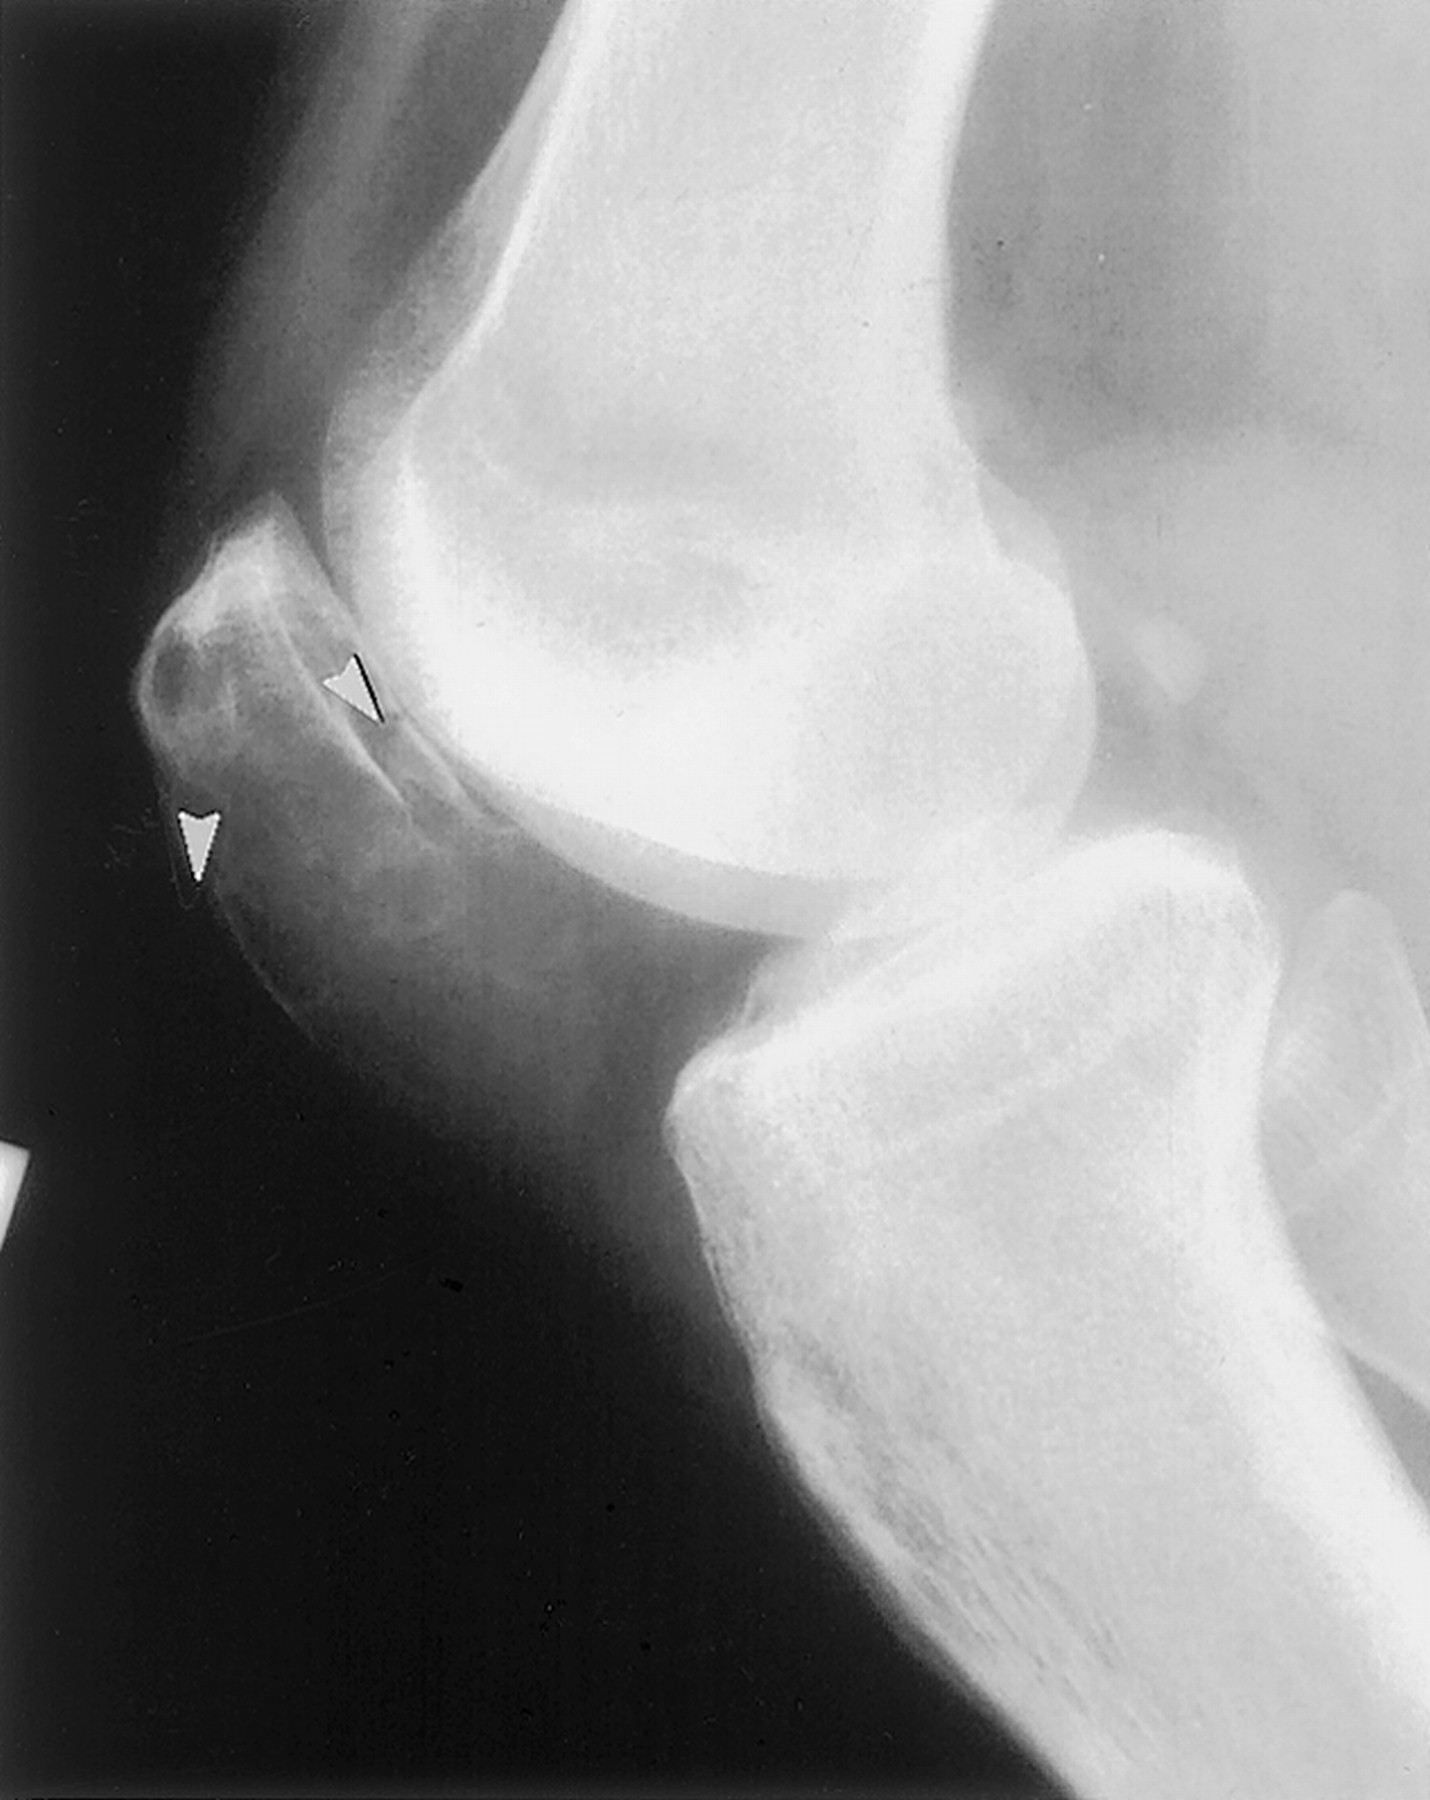

Гигантоклеточная опухоль.

Злокачественная гигантоклеточная  опухоль возникает из доброкачественной (частота 10-20%). После операции возможно появление рецидива опухоли.